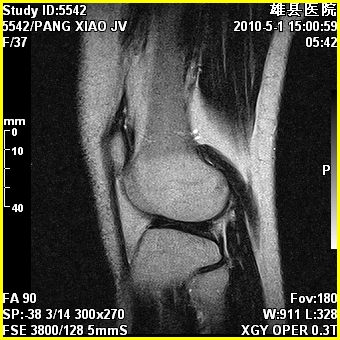

右股骨下端前内侧类圆形异常信号,位于干骺端,呈长t1长t2改变,但信号不均,t1图上病灶中心见小片状稍高信号影,t2图上见散在稍低信号影,stir像呈高信号,因病灶较小,缺乏特征性改变,结合患者年龄及部位,考虑嗜酸性肉芽肿可能性大。胫骨关节面下的小囊状异常信号,如果一元论考虑则为嗜酸性肉芽肿,不过发生在这个部位的少见,二元论考虑为邻关节骨囊肿。半月板与前后交叉韧带均未见异常。